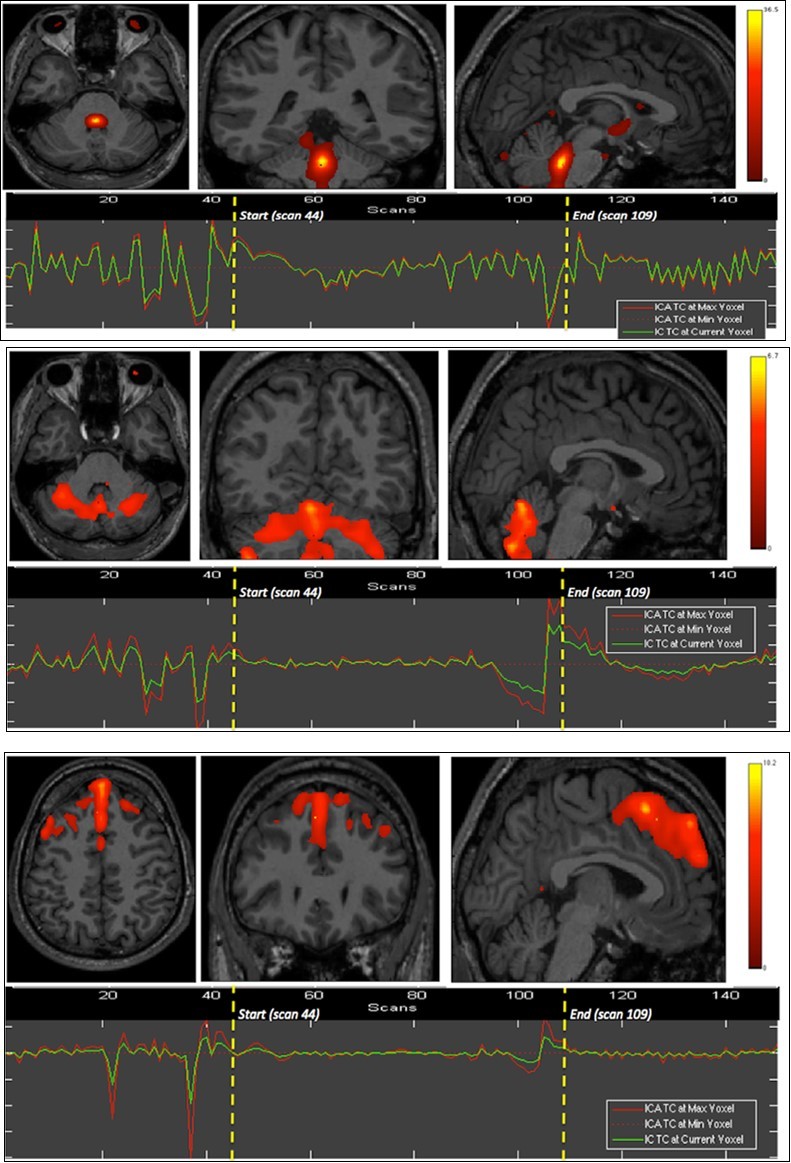

We found the dorsal pons, cerebellar hemispheres (superior aspect) and whole vermis, bilateral dorsal and ventromedial prefrontal, and medial occipital cortices to show significant BOLD signals differences as compared to the whole brain, during the first breath holding (Figure 1).

Figure 1.First experiment showing both BOLD signal time courses and activated areas: dorsal pons (1st row), anterior and posterior vermis as well as superior and lateral aspects of the cerebellar hemispheres (2nd row), dorsomedial prefrontal cortex (3rd row), and primary visual cortex (last row).

The apnea period was obviously recognizable on the time course of the BOLD signals graphs because of the striking change of the curves from breathing to apnea and after apnea, with very low fluctuations during apnea. Within eloquent brain areas TC curves showed various patterns: (i) high fluctuations mainly in the second half of apnea in the dorsal pons only (Figure 1-1st row), (ii) very low fluctuations with deep depression at the end of apnea in the cerebellum (Figure 1-2nd row) as well as in the supramarginal gyrus (Figure 2, lower row), less marked in occipital areas (figure 1-4th row), and (iii) flat curve in dorsomedial prefrontal (Figure 1-3), ventromedial prefrontal (Figure 2-upper row) and inferior parietal areas (Figure 2-middle row). The eloquent areas disclosed during both experiments are mapped on a brain mesh as nodes of both networks (Figure 3).